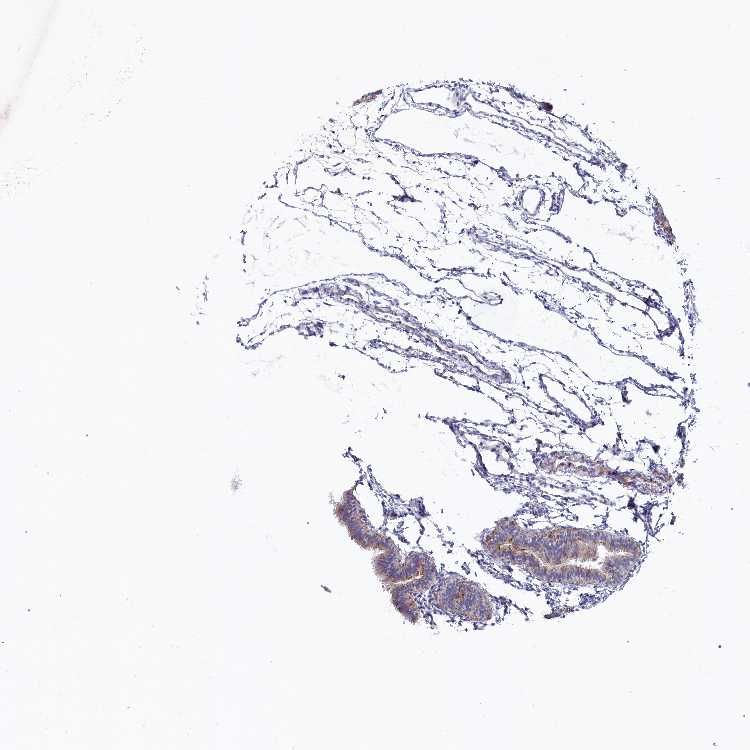

FALLOPIAN TUBE - Antibody stainingi

Antibody staining in the annotated cell types in the current human tissue is reported as not detected, low, medium, or high, based on conventional immunohistochemistry profiling in selected tissues. This score is based on the combination of the staining intensity and fraction of stained cells.

Each image is clickable and will lead to virtual microscopy that enables deeper exploration of all samples and also displays staining intensity scores, fraction scores and subcellular localization as well as patient and tissue information for each sample.

Antibody HPA042042

Ciliated cells (cell body) Not detected

Ciliated cells (cilia axoneme) Not detected

Ciliated cells (ciliary rootlets) Medium

Ciliated cells (tip of cilia) Not detected

Non-ciliated cells High